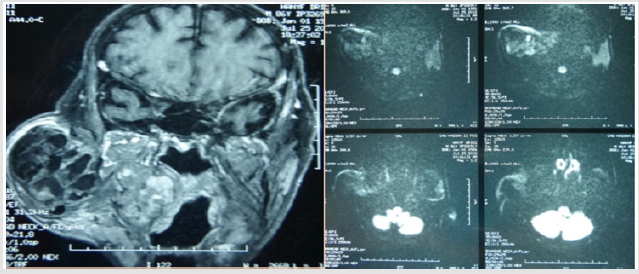

Benign tumors account for 80% of all of our patients, dominated mainly by pleomorphic adenoma followed by whartin tumor. There were 8 cases of cancer that were of a diverse nature (Table 1). Cervical ultrasound was performed in 18 patients. Computed tomography in 20 patients (44% of the cases), generally in the face of very large tumors initially in order to specify their depth extension. Magnetic resonance imaging was realized for 39 patients (Figures 1 & 2). We studied the morphological and functional MRI criterias of the pleomorphic adenomas of our patients, warthin tumors and malignant tumors, then we established different criterias associations and their predictability of the final histological result of the tumor.

Figure 2: MRI image in axial and coronal section in T1-weighted and diffusion sequences of a malignant tumor of the right parotid.

The Association: Low signal intensity on T1, high signal intensity on T2, apparent diffusion coefficient superior to 1,5 and positive enhancement after injection of contrast product, was significant in predicting the histological diagnosis of pleomorphic adenoma, with a specificity 100% of and a sensibility of 83%. The association: low signal intensity on T1, irregular lesion limits, apparent diffusion coefficient inferior to 1 and extra parotid extension, was significant in predicting the histological diagnosis of malignant tumors with a specificity of 100% and a sensibility of 67%. However no statistically significant association was found for the cases of warthin tumors. The MRI histological correlation predicting the benignity or malignancy of the parotid tumor showed that for a total of 39 MRI results, the correlation was statistically significant (p< 0.001) with a sensibility of 100% and specificity of 94,1%. Furthermore, the MRI histological correlation predicting the diagnosis of pleomorphic adenoma was statistically significant (p< 0.001) with a sensibility of 90% and specificity of 86,7%.